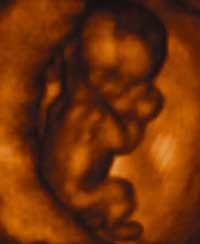

Dr. Jerome Lejeune, “Father of Modern Genetics” and discoverer of the cause of Down’s Syndrome, stated, “To accept the fact that after fertilization has taken place, a new human has come into being is no longer a matter of taste or opinion . . . it is plain experimental evidence.”

In the widely used medical textbook, The Developing Human, Clinically Oriented Embryology, 6th Edition, Moore, Persaud, Saunders, 1998, states on page 2 that “The intricate processes by which a baby develops from a single cell are miraculous …. This cell [the zygote] results from the union of an oocyte [egg] and sperm. A zygote is the beginning of a new human being ….” On page 18 this theme is repeated: “Human development begins at fertilization ….”

“The unborn baby is alive from the first moment of conception of a single egg and a single sperm.” N.Z. Health Department: Pamphlet No 83 Your New Baby (Government Printer) 1969.